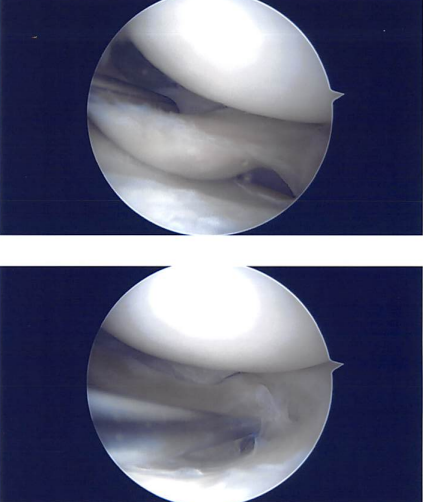

Examination of the lateral compartment showed tearing of the lateral meniscus and sutures were present. The lateral meniscus was debrided with the use of upbiter, straight biter, and shaver. A thorough debridement was performed. There was some amount of arthritis of the tibial cartilage.

Balanced margins were achieved. Almost 40% of lateral meniscus was resected in the procedure to achieve balanced margins. Final pictures were taken and saved. The examination of the compartment showed no arthritis. Final pictures were taken and saved. The knee was thoroughly irrigated and drained.

Intraoperative images